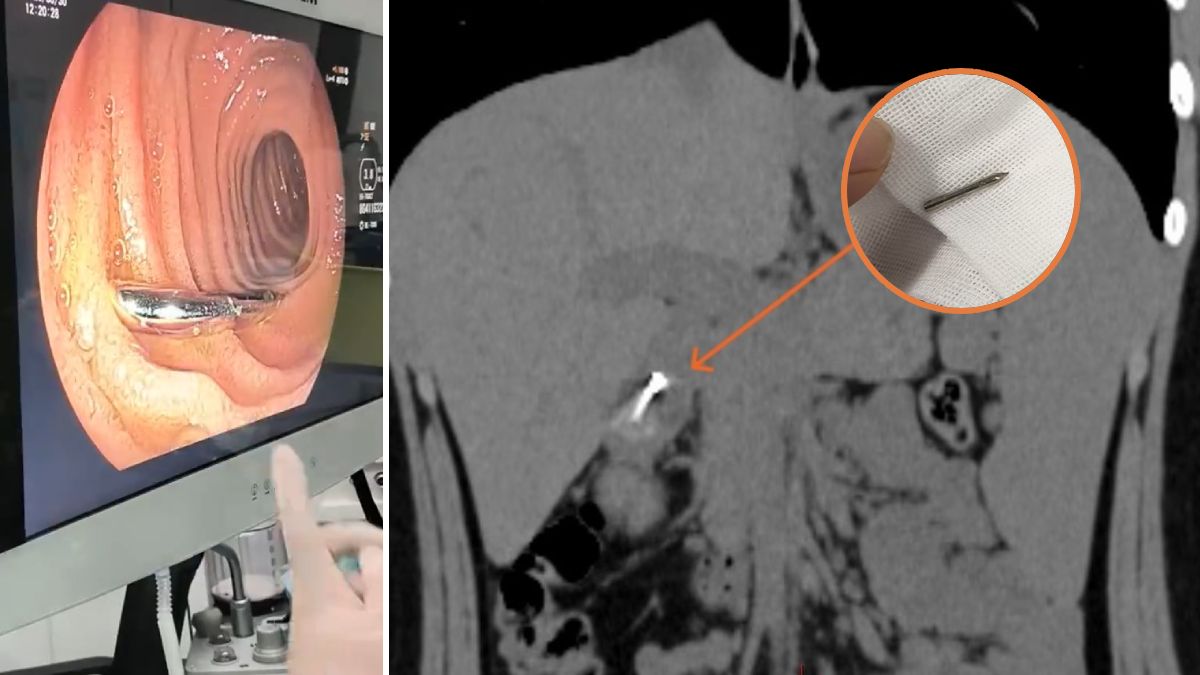

上堂「發吽哣」隨時惹殺身之禍?江蘇揚州一名初中男生,日前在課堂上思考問題時,竟不自覺含著圓規把玩,結果不慎吞下長達1.9厘米的鋒利針頭。由於初中生年紀尚輕且未有禁食,手術風險極高。幸得醫護團隊藝高人膽大,成功取出尖針,化解穿腸危機。 內地「荔枝新聞」報道,事發於3月31日,就讀中學的小劉(化名)原本正在上堂,一時分神,竟吞下原本含在嘴裡的圓規針頭。大驚失色的他即告知老師,隨後被送往揚州市江都人民醫